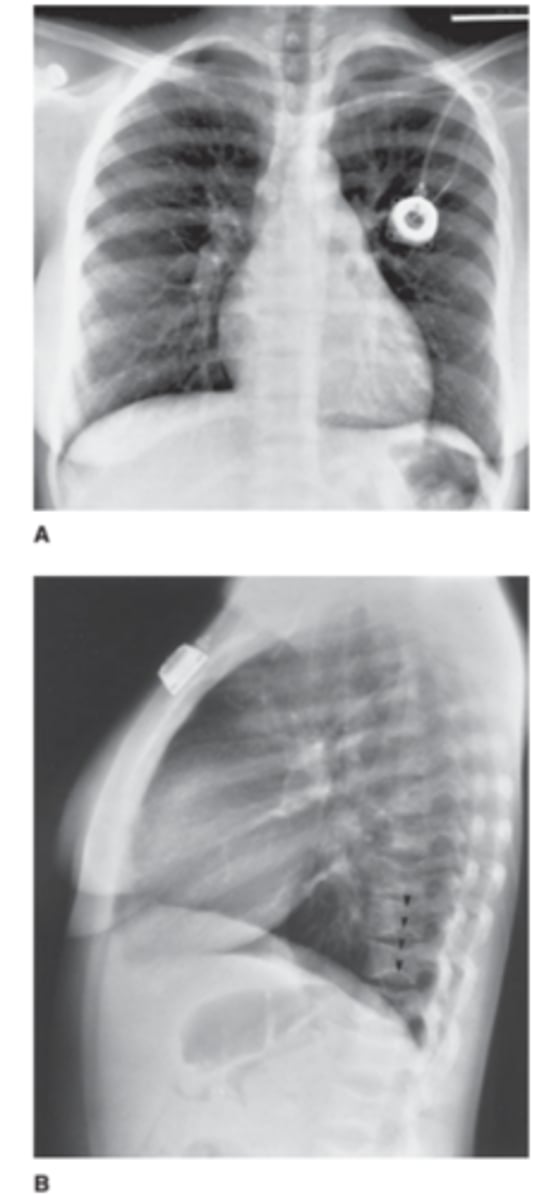

Infant with low-grade fever. You obtain a chest radiograph to evaluate for pneumonia (frontal view of the chest).

You interpret the chest radiograph for Case 6-2

(Figure 6-9) and render the following opinion:

A. Normal chest radiograph

B. Round pneumonia

C. Healing rib fractures

D. Pneumothorax

answer

C.

Unfortunately these are healing rib fractures in an infant (note the calluses). Suspected child abuse and an immediate CPS call.